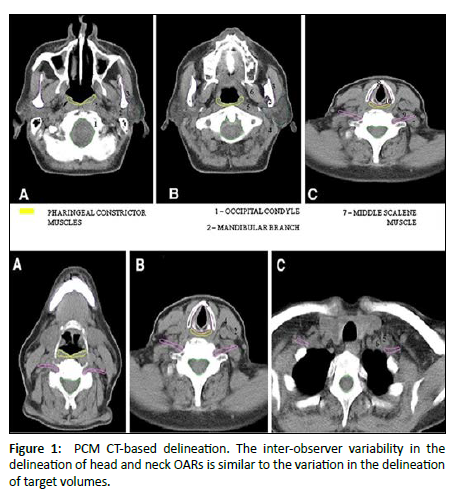

- Understandability of speech: This scale was scored on the basis of how well the interviewer understood the patient during the conversation [23] [Figure 1].

Figure 1: PCM CT-based delineation. The inter-observer variability in the delineation of head and neck OARs is similar to the variation in the delineation of target volumes.